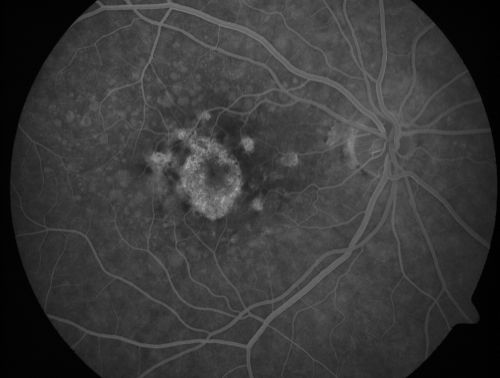

| Album name: | scohen125 / Geographic Atrophy - Previous Confluent Soft Macular Drusen |